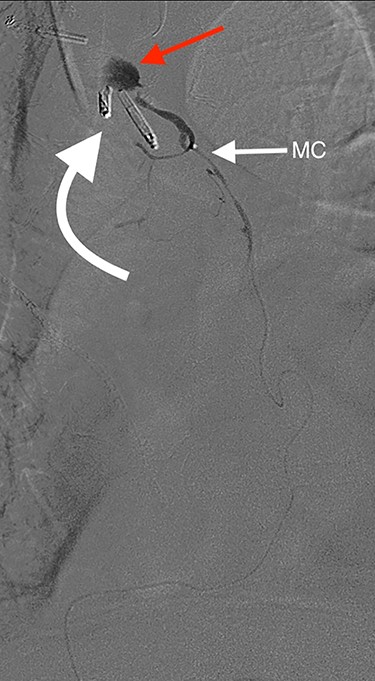

Angiography of the right gastro-epiploic artery. Arrowhead = celiac trunk; Arrow = right gastro-epiploic; Curved arrow = OG anastomosis.

Eight days later, he represented with an upper gastrointestinal bleed with massive haematemesis requiring immediate intubation for airway protection. Computer tomography angiography was unremarkable and an emergency gastroscopy revealed an extensive amount of blood and clot in the oesophagus and gastric conduit (limiting the view), but no active bleeding point. Conservative treatment in the Intensive Care Unit (ICU) with blood transfusion, proton pump inhibitors and life support were implemented. Another large bleed occurred 2 days later and a repeat gastroscopy revealed a non-bleeding visible vessel at the OG anastomosis and a haemostatic clip was applied. However, over the next 10 days, the patient remained blood transfusion dependent and had two further endoscopies. The first was unremarkable, but the second endoscopy re-demonstrated the luminal vessel at the OG anastomosis, with no evidence of the previously placed clip. This was felt to be the cause of his intermittent and problematic bleeding, so another haemostatic clip was attempted, resulting in pulsatile, moderate volume arterial bleeding. The procedure was abandoned and the patient transported immediately to the Interventional Radiology Suite. Right femoral access was obtained and angiography performed. The thoracic aorta was normal, so the celiac trunk was cannulated and angiography of the right gastro-epiploic artery performed (Fig. 1), revealing active extravasation of contrast at the OG anastomosis as shown in Fig. 2. A microcatheter was advanced along the length of the right gastro-epiploic artery to the OG anastomosis and coil embolization was performed (Fig. 3). Care had to be taken to ensure that the embolization was as distal as possible to limit the risk of ischaemic complications. The patient required lengthy ongoing care in the ICU for organ dysfunction but remained hemodynamically stable after embolization without evidence of conduit ischaemia. His hospital stay was obviously lengthy, but he was ultimately transferred to a rehabilitation unit.

Oesophagectomy is a major operation with significant perioperative morbidity. Respiratory and cardiac complications, along with gastric conduit ischemia and anastomotic leak, tend to dominate [3]. However, bleeding complications apart from those occurring intra-operatively are rarely reported [1, 2]. We present a unique case of an anastomotic bleed from a terminal branch of the gastro-epiploic vascular arcade. While the origin of this vascular arcade is a defined vessel (right gastric-epiploic artery) visible to the naked eye, the terminal portion is comprised of submucosal arterioles and capillaries and often devoid of a visible vessel [4]. However, as shown in Fig. 1, vascular supply to the terminal portion of the gastric conduit is present and can be abundant. The bleeding in this case likely occurred from incorporation in the anastomosis of either an invisible submucosal arteriole or the terminal portion of the right gastro-epiploic artery hidden within omental tissue. It is our standard practise to construct the OG anastomosis with the EEA circular stapler. It is common surgical knowledge that the oesophageal wall is thick [5] and has been our practise to use the 4.8-mm EEA staple height. There are several descriptions in the literature about this anastomotic technique and most recommend this staple height [6–8]. However, we believe that the higher staple height may have contributed to the bleeding issue in this case as there may have been insufficient compression of a submucosal arteriole. While it is impossible to be certain if a lower staple height would have prevented this situation, this case has resulted in our change to use the 3.5-mm EEA. In addition to this, we have become more meticulous in ensuring that the portion of the great curvature to be used for the anastomosis is cleared of excessive omental tissue to be sure no visible vessel is present that may get caught in the anastomosis.